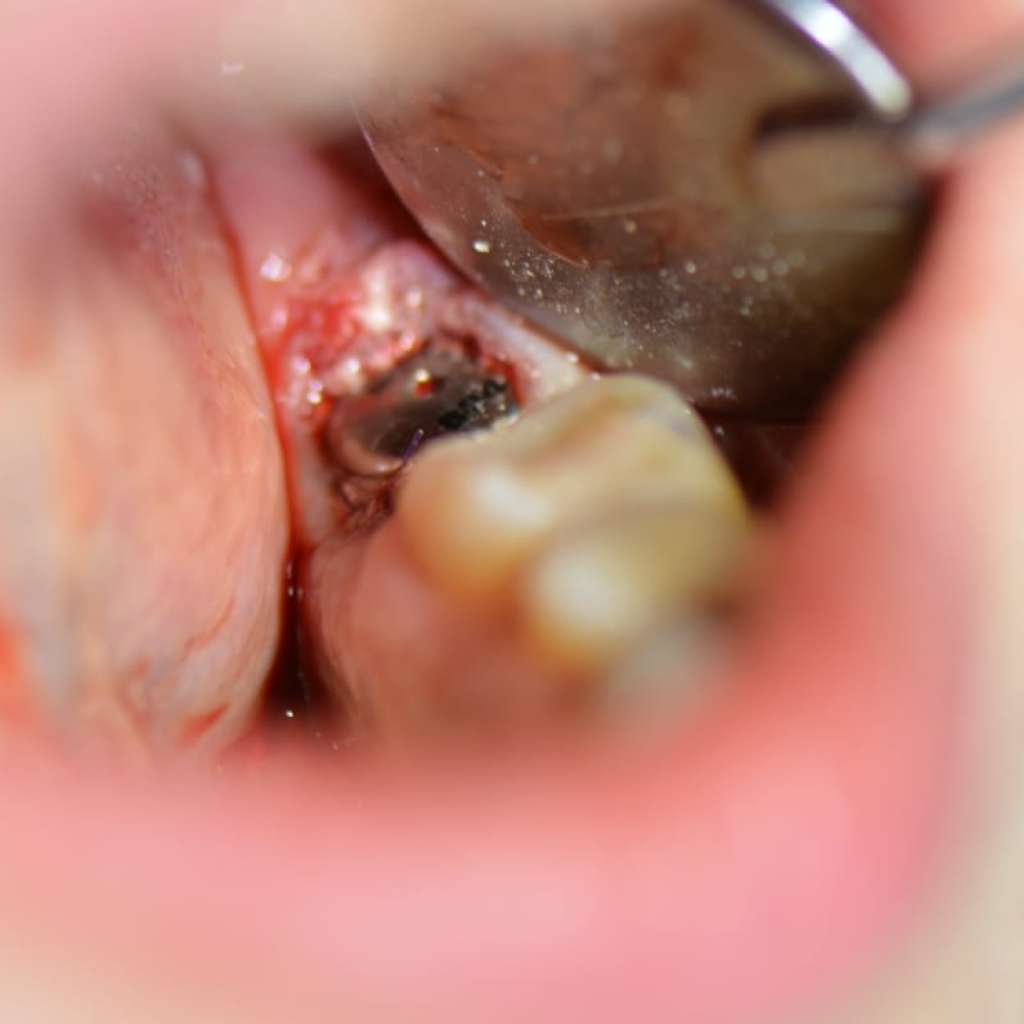

Пациентке по терапевтическим показаниям были удалены зубы 37 и 47.

- Атравматичное удаление зуба